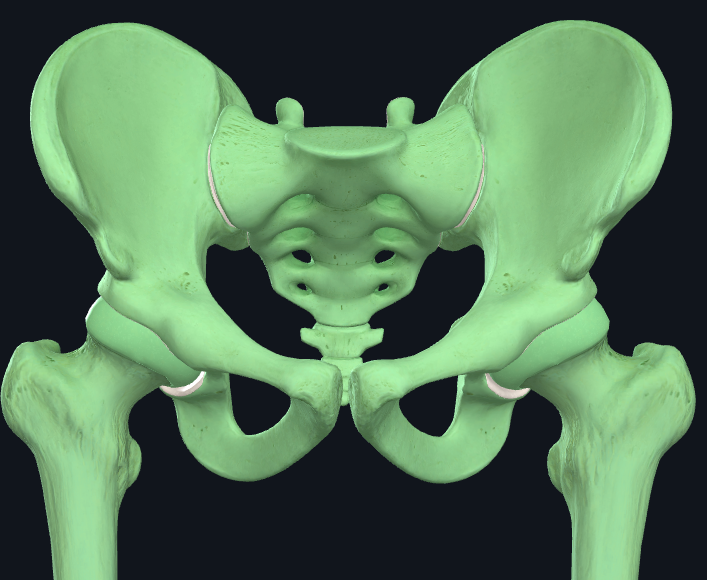

Articulations of the hip bone

Sacrum and ilium - to form sacroiliac joint.

Pubes - to form pubic symphysis

Acetabulum and femur - to form hip joint

What three bones make up the hip bone?

1) Ilium - largest bone of the three

2) Ischium - sits inferiorly to the ilium

3) Pubis - inferiormedially to the ilium

These bones join at the tri-radiate cartilage that is found in the acetabulum. This cartilage fuses at around 15-17yo.